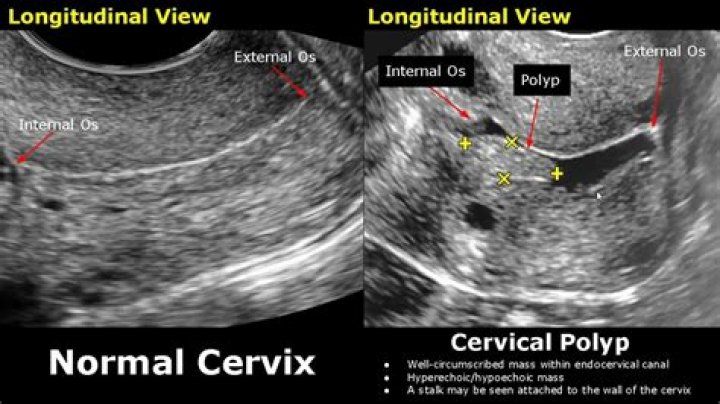

There are two main portions of the cervix: The part of the cervix that can be seen from inside the vagina during a gynecologic examination is known as the ectocervix. An opening in the center of the ectocervix, known as the external os, opens to allow passage between the uterus and vagina.